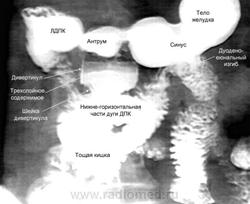

Нашел несколько картинок в реферате, который готовил на аттестацию. Рентгенограммы и эндофото выставлены просто для примера, относятся к разным пациентам.

1. пацеинт с инфильтративным раком желудка, на который я не сразу обратил внимание, отвлекшись на интересный дивертикул ДПК

2. Пациент с тотальным инфильтративным раком желудка. Паллиативный передний ГЭА был наложен в бытность только антрального распространения опухоли. На момент РС инфильтрация, похоже, затрагивает и сам анастомоз.